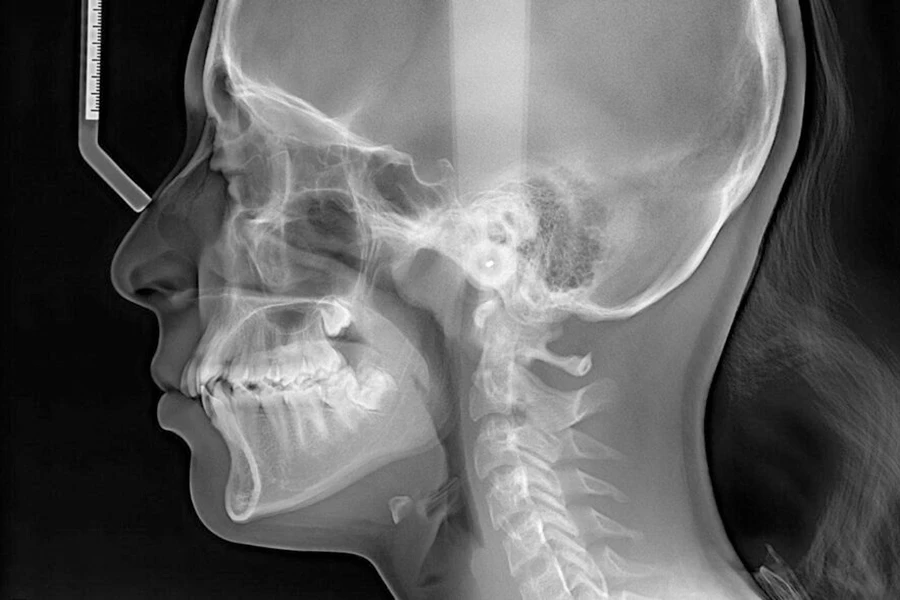

تجهیزات تصویربرداری نقش بنیادین در تشخیص دقیق مشکلات فک و دندان دارند و بدون آنها امکان برنامه ریزی ایمن و موثر برای جراحی وجود ندارد. در دندانپزشکی امروزی، استفاده از تکنولوژی های پیشرفته مانند سی بی سی تی، رادیوگرافی پانورامیک دیجیتال و تصویربرداری سه بعدی توانسته است میزان خطا در تشخیص را به حداقل برساند. سی بی سی تی به دلیل ارائه تصاویر سه بعدی با دقت بسیار بالا یکی از ضروری ترین ابزارها برای جراحی ایمپلنت، جراحی ارتوگناتیک و بررسی ضایعات فکی است. این دستگاه ها به جراح اجازه می دهند که ساختار های حیاتی مانند کانال عصب فک پایین، سینوس ماگزیلا و تراکم استخوان را به طور دقیق مشاهده کند و از آسیب های احتمالی جلوگیری شود. همچنین این روش تصویربرداری نسبت به سی تی اسکن بیمارستانی دوز اشعه بسیار کمتری دارد و برای بیماران مناسب تر است.

تصویربرداری پانورامیک دیجیتال نیز یکی از ابزارهای پرکاربرد در کلینیک های دندانپزشکی است و اطلاعات مهمی درباره وضعیت دندان های عقل نهفته، ضایعات استخوانی و موقعیت ریشه ها ارائه می دهد. در مقالات جدید، تاکید زیادی بر استفاده از سیستم های دیجیتال به جای رادیولوژی قدیمی شده است زیرا این روش ها علاوه بر کاهش اشعه، امکان پردازش تصویر برای افزایش دقت تشخیص را فراهم می کنند. همچنین تصاویر قابل ذخیره، ارسال و آرشیو هستند. به طور کلی این تجهیزات پایه ای ترین و مهم ترین ابزار برای هر نوع جراحی فک و دندان محسوب می شوند و کیفیت درمان بدون آنها کاهش می یابد. تحقیقات اخیر انجمن جراحان فک و صورت آمریکا نیز نشان می دهد که استفاده از این تکنولوژی ها احتمال عوارض جراحی را تا 35 درصد کاهش می دهد.